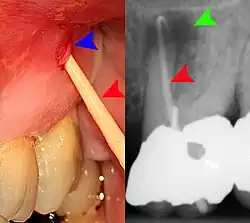

- Radiographs utilized to find dental caries and bone loss laterally or at the apex.

Decay (green) with apical abscess (blue) -

Gutta-percha point indicating abscess origin